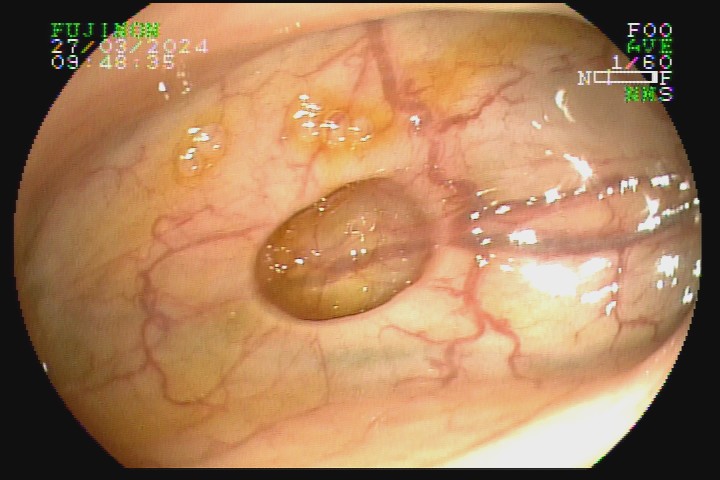

A diverticulose é uma doença adquirida, frequente entre pessoas mais idosas. Acredita-se que tenha como principal fator etiológico hábitos dietéticos relacionados com o refinamento da dieta industrializada. Pode ter uma evolução benigna por toda a vida e ser totalmente assintomática, mas pode também caracterizar-se como doença de sinais e sintomas agressivvos, com considerável morbidade e mortalidade devido às suas principais complicações: inflamação e sangramento.

A diverticulose cólica é consequência da herniação da mucosa do intestino grosso por entre as fibras musculares da parede intestinal. A diverticulose do cólon esquerdo complica mais com inflamação, e a diverticulose do cólon direito complica mais com sangramento.